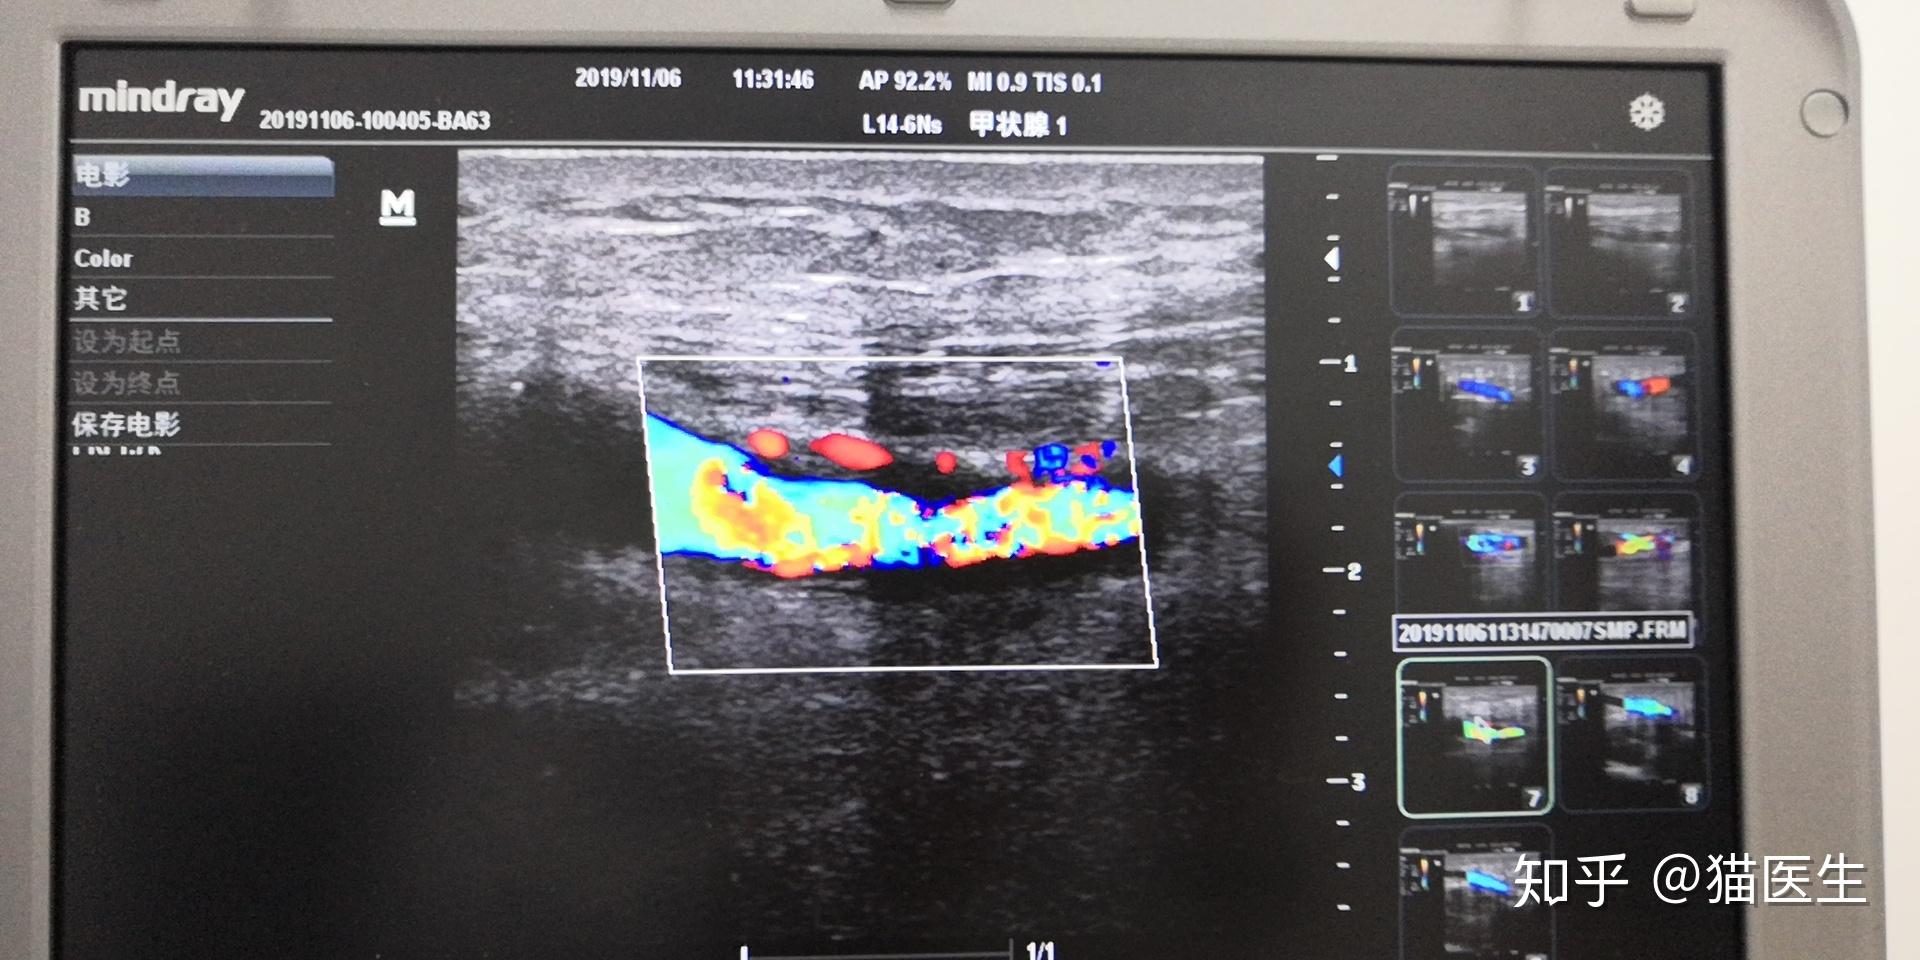

彩超引导下穿刺左侧头静脉